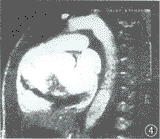

图4 同图2病例,左前斜位瘘口层面电影MR成像显示瘘口及湍流引起的信号丢失